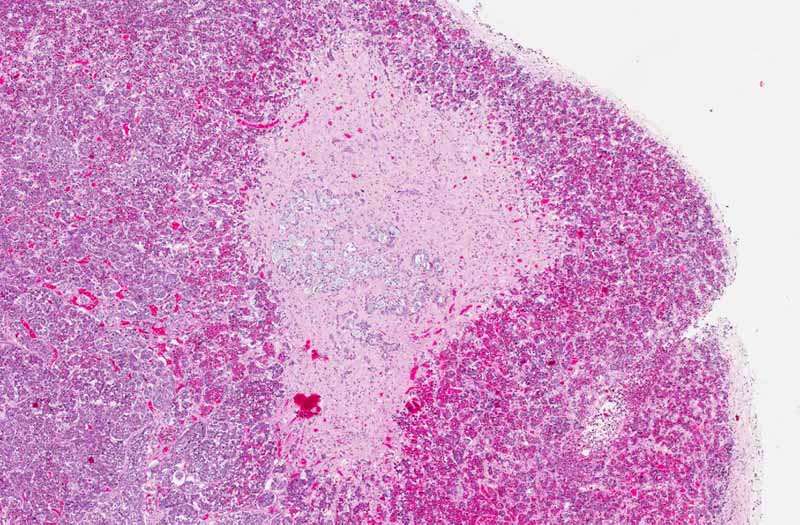

Area 2: Note that less prominent mucin producing glands are found at the interface between the neurohypophysis and adenophysis, a more typical location for these ectopic glands.

• The image being shown here is largely composed of the anterior pituitary. Portion of the posterior pituitary is also present. The nests of epithelial glands in the anterior are rather monotonous in size and there is no evidence of hyperplasia or adenoma formation. Second, they are associated with a substantial amount of fibrosis. This raises a possibility of metastatic adenocarcinoma but no cancer is found on autopsy.

• Ectopic salivary glands should not be mistaken as metastatic carcinoma. These glands are typically found on the surface of the pituitary or in the neurohypophysis, often at the interface between the neurohypophysis (posterior pituitary) and adenohypophysis (anterior pituitary) just posterior to the pars intermedia. They are composed of single layer of columnar or cuboidal epithelium with finely granular cytoplasm that is PAS positive. Oncocytic changes is also often. Mucin producing cells can also be present as illustrated in this case. What is unusual in this case is that there is also fibrosis around these glands.